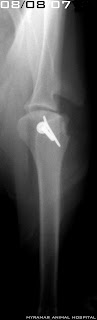

Tras las radiografías pertinentes se diagnostica una Salter Harris IV distal humeral. Fractura a través de la epífisis, fisis y metáfisis humeral distal izquierda.

La estabilización de la fractura se realiza utilizando un tornillo de compresión transcondilar de 3.5mm + un tornillo de neutralización antirrotacional de 2.0mm.

Se presenta evolución radiográfica del caso